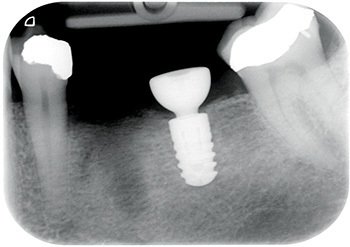

Well, Frances moved to the other side of the country, but I used to see her initially once a year and then every two years, free of charge, just so I could post updates of the case to Dentaltown. As you can see from the most current X-rays, not only has the implant survived, but the bone around the implant (what many worried would be overloaded and lost) looks even better in 2024 than it did in 2009 when the implant was first restored!

Figs. 8–10: Fifteen years after restoration.

One might expect the loading of the bone around a short implant supporting both a molar and a premolar restoration to be really quite high. Classic teaching suggests bone responds to overload by resorbing. But the bone around this implant looks even better after 15 years of overload than it did when it was first restored.

Perhaps we expect too little of the bone around implants. Perhaps, just like muscle, bone responds to loading by becoming stronger, which explains why Frances’ implant X-ray shows better bone levels after 15 years.